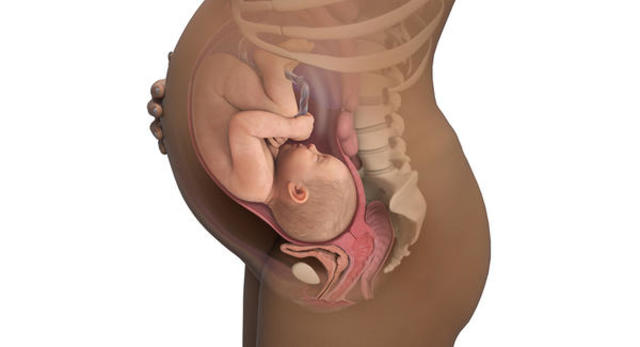

Continúa creciendo y almacenando grasa subcutánea y carbohidratos en el hígado en preparación a la recta final antes del parto. El útero materno ha crecido mucho y llega casi hasta las costillas inferiores, la respiración es cada vez más dificultosa y la pesadez, la torpeza y la impaciencia han crecido considerablemente. Los movimientos del bebé -bebé que casi ha completado su desarrollo en todos los órganos necesarios, ya pesa 2383 gr y mide 46 cm.

• Semana 36

Semana 36

El bebé está a un paso de graduarse de "maduro", sigue creciendo y engordando aprovechando sus últimas semanas de alimentación y comodidad sin esfuerzos. La mayor parte de los bebés han madurado para este momento pero seguimos dándole el remoquete de parto prematuro si llegase a nacer en este momento; esto es por convencionalismo, para que todos hablemos el mismo idioma. El líquido amniótico es claro y sin bilirrubina. Pesa 2622 gr y mide 47 cm